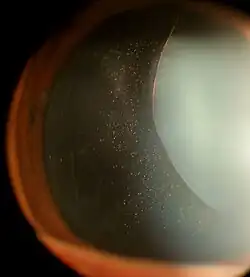

| Ectopia lentis in a patient with Marfan syndrome. Zonular fibers are visible. | |